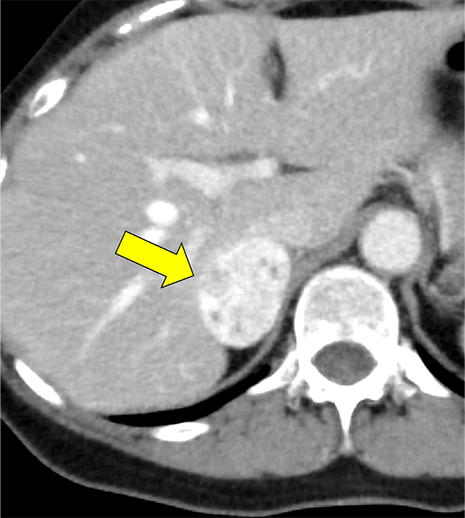

本例は、偶発的に指摘された右副腎腫瘍である。高血圧はあるが内服せず経過観察されている患者で、1cm/5年程度の非常に緩徐な増大を示す多血性の腫瘍を認める。腫瘍はI-123MIBGシンチ陰性であり、内分泌内科での精査においてもホルモン産生を疑う所見に乏しく、褐色細胞腫よりも海綿状血管腫が疑われていた。しかし、増大傾向があり破裂や出血のリスクなども考慮されて手術の方針となった。手術中に血圧の変動を認め、病理で褐色細胞腫の診断となった。

褐色細胞腫は副腎髄質に存在するクロム親和性細胞に由来する腫瘍で、カテコールアミンなど種々の生理活性物質を産生する。ダイナミック造影で動脈相での強い濃染と持続する造影効果が特徴とされ、サイズが大きい病変は嚢胞変性や出血、壊死を伴うことが多い。かつては、臨床的に褐色細胞腫が疑われる場合、ヨード造影剤の投与はカテコールアミンの過剰放出を誘発し、高血圧クリーゼを引き起こす可能性があるため原則禁忌とされていた。しかし、現在汎用されている非イオン性・低浸透圧性造影剤であればこの現象は起こらないとの報告もあり、European Society of Urogenital Radiology Guidelines on Contrast Media, ver 10.0では、「経静脈的ヨード造影剤の投与をする場合でも特別な準備の必要はない」と記載されている。イオプロミドの電子添文上は、禁忌にはなっていないものの、「慎重に投与すること」との記載になっている。本例では、血管腫疑いとして合計5回の造影CTが行われているが、血圧変動や頭痛、動悸などの症状は一度も認められなかった。

本例の画像所見として、褐色細胞腫としてダイナミック造影の濃染パターンは典型的ともいえたが、大きさの割に変性が乏しい点、MIBGシンチでの核種集積に乏しい点、ホルモン産生に乏しい点など非典型的な要素が複数存在し、海綿状血管腫を除外しきれなかった。なお、褐色細胞腫はRET遺伝子変異による多発性内分泌腺腫症(multiple endocrine neoplasia;MEN)type 2A・2B、VHL遺伝子によるvon Hippel-Lindau病、NF1遺伝子による神経線維腫症1型に生じることが知られているが、これらの疾患を想起させるような他病変は本例には見つかっていない。

腺腫や骨髄脂肪腫など良性と断定できない副腎腫瘍の鑑別をする際、大きい病変であれば褐色細胞腫や副腎癌、悪性リンパ腫などが考慮される。核医学検査も有用ではあるが、本例のように偽陰性となることも稀にあり、その際はダイナミック造影パターン、血管への浸潤、転移の有無などから判断しなければならない。適切なタイミングで撮像されたダイナミック造影CTは、多血性病変であるかの評価、周囲の血管との関係性、多血性の転移巣の有無などの判断に寄与し、診断の重要な手がかりとなると考える。